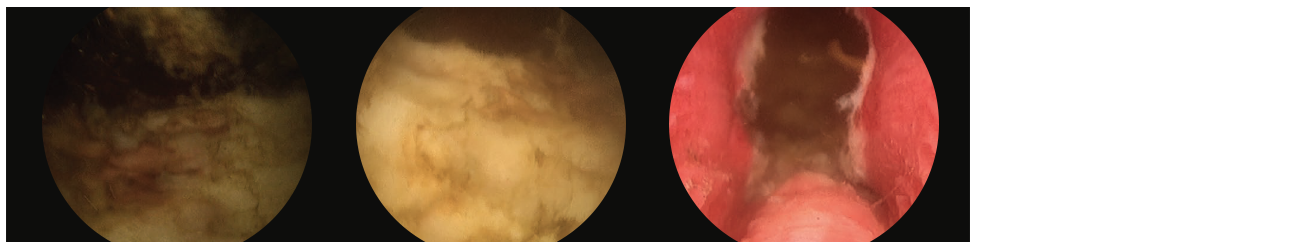

3 scope images. Identifying verumontanum. Figure 3, Part 1: VIT along capsule of floor tissue.

Additional 3 scope images. Identifying verumontanum. Figure 3, Part 2: VIT along capsule of floor tissue.